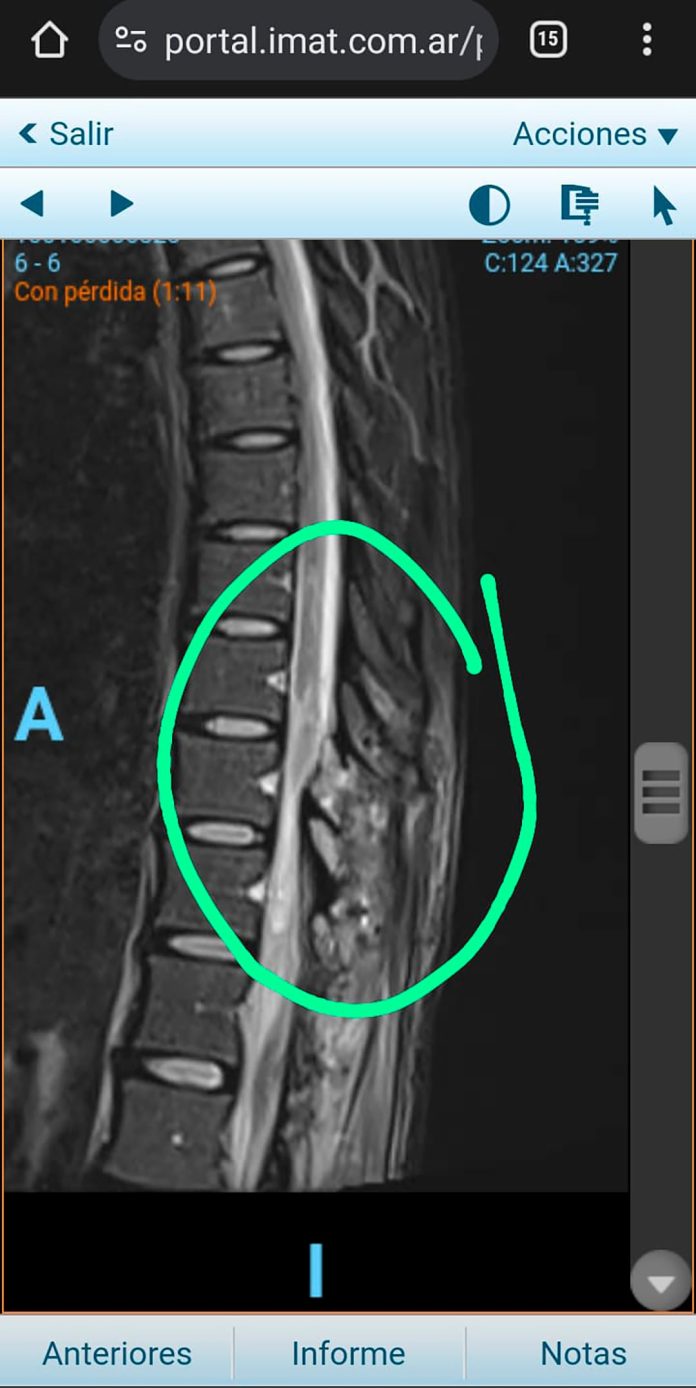

La verdad no se supo hasta 45 días después, cuando, luego de mucha insistencia de parte de sus familiares, logró que le hicieran una resonancia. El estudio demoró porque, según quedó asentado en la denuncia que luego radicó su papá, el jefe del sector de Neurocirugía del Hospital de Clínicas no la pidió alegando que Yañez no la había requerido.

El diagnóstico llegó recién el 2 de marzo: Antonella tenía una “apófisis espinal que le estaba comprimiendo la médula”. Esto significa que, tras la operación, una parte del hueso de la columna quedó haciendo una presión que le ocasionaba diferentes problemas. Por eso tuvieron que intervenirla de urgencia para descomprimir el canal medular.

“Si me hubieran hecho el estudio de forma inmediata y la descompresión a tiempo, mi lesión no sería tan grave”, dice la joven, recordando que estuvo más de un mes con la médula anclada. Hoy, a casi dos años del hecho, Antonella todavía no puede mover las piernas, no tiene sensibilidad al tacto y no puede ir al baño. “Hasta el día de hoy me realizo cateterismo intermitente porque no puedo orinar por mis medios”, cuenta.